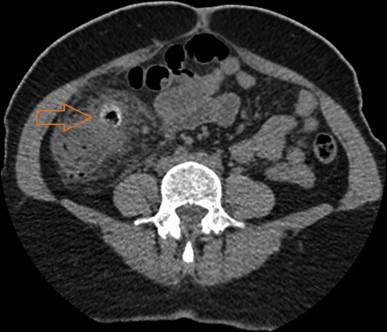

A total of 632 patients with colonic diverticulitis were admitted to our institution over a seven-year period, of which 13 patients had caecal diverticulitis (2.06%). Of the 13 patients, twelve were of Asian background and ten were considered young (≤50 years of age). The main complaints were right sided abdominal pain (n = 11, 84.6%) and diarrhoea (n = 5, 38.5%). Nine were diagnosed using computed tomography (n = 9/10, 90%), three on laparoscopy and one using ultrasound (n = 1/2, 50%). Ten patients were treated successfully by conservative means.

在七年期间,共有632例结肠憩室炎患者入住我院,其中13例患有盲肠憩室炎(2.06%)。在这13例患者中,12例具有亚洲背景,10例被认为是年轻人(≤50岁)。主要症状为右侧腹痛(n = 11,84.6%)和腹泻(n = 5,38.5%)。9例通过计算机断层扫描确诊(n = 9/10,90%),3例通过腹腔镜检查确诊,1例通过超声检查确诊(n = 1/2,50%)。10例患者通过保守治疗成功治愈。